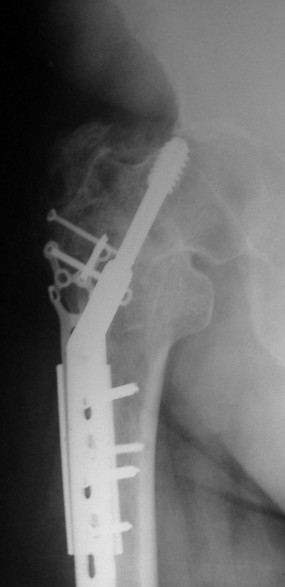

Уважаемые коллеги, каково ваше мнение по поводу необходимости удаления металлоконструкций в данном случае - мужчина, 53 лет, сопутстувующая патология - схараный диабет 2 типа, впервые выявленный, ГБ 1-2 ст., хр.калькулезный холецистит, хр.гепатит. Операция произведена в январе 2009 г. через 18 сут. после получения травмы.